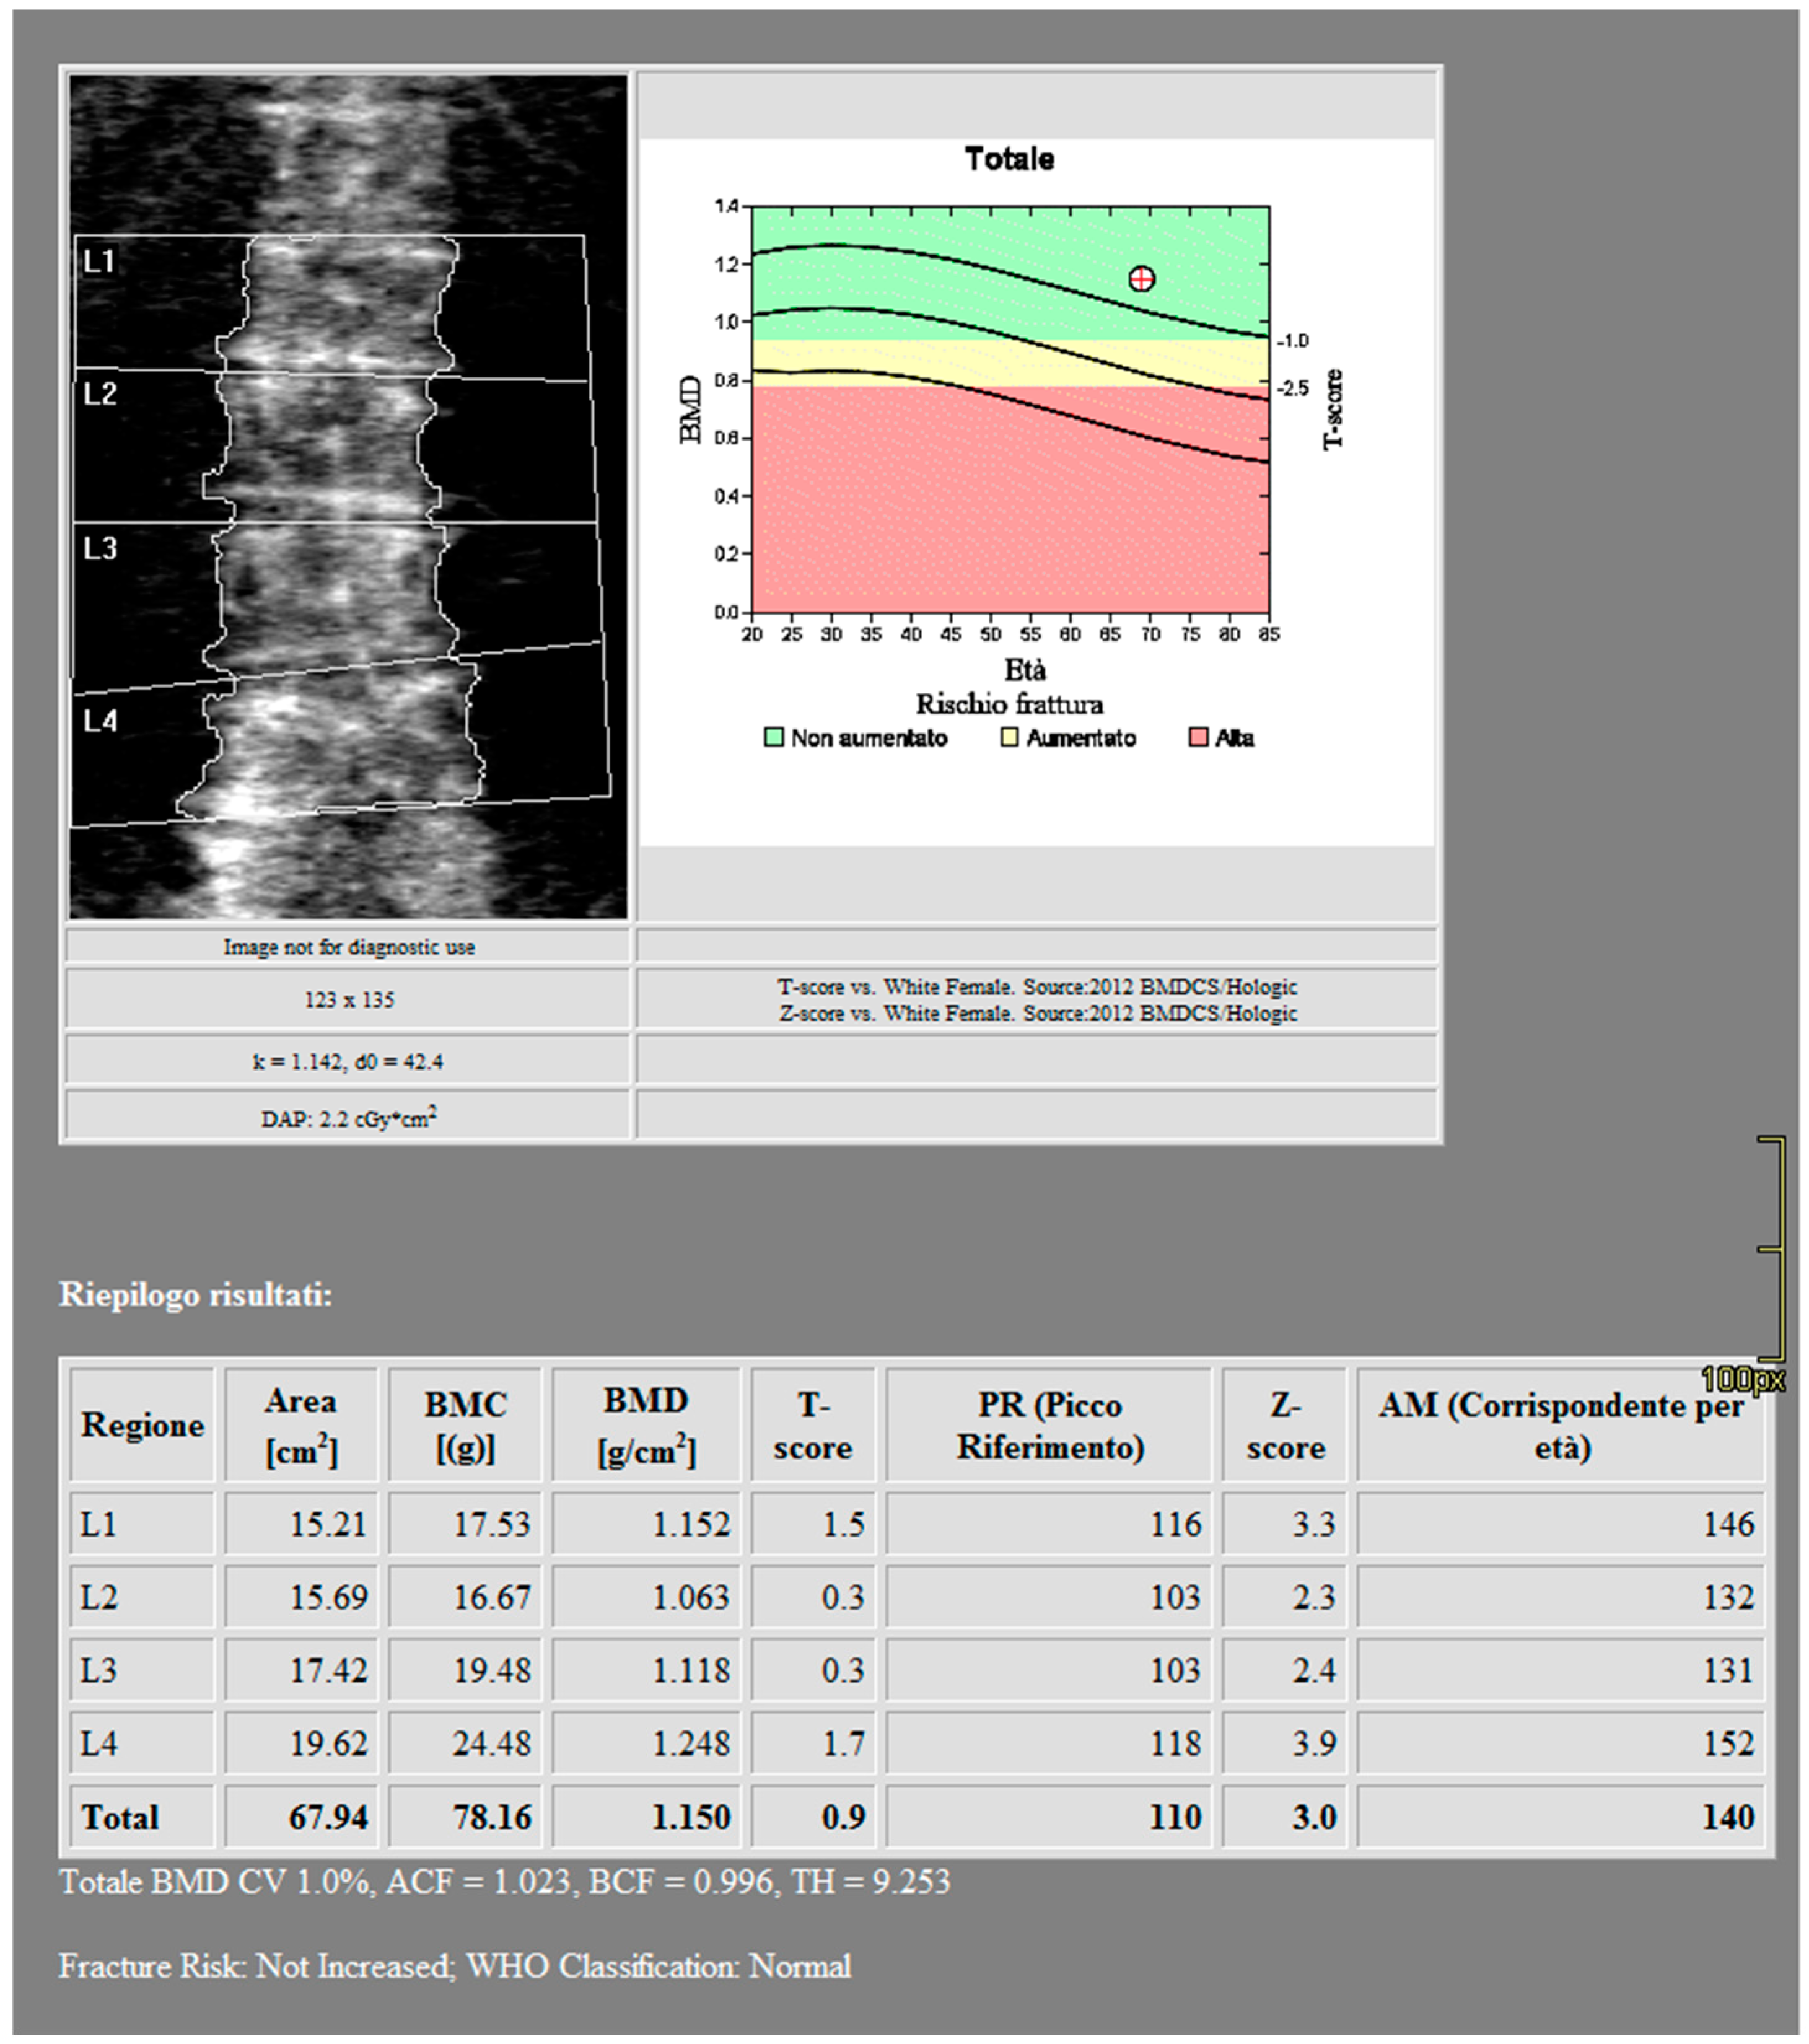

2.2. Imaging

2.3. Postprocessing

3. Results